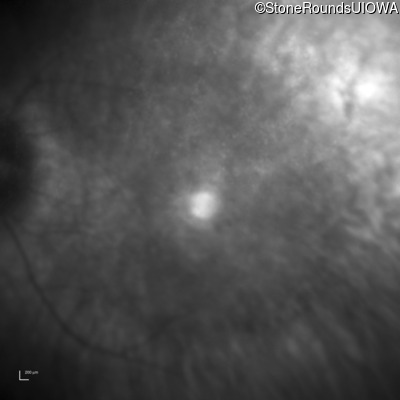

Age at visit: 59 years